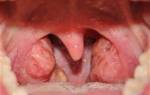

Как выглядит горло после операции?

После удаления гланд на их месте сначала возникают большого размера пятна. Цвет – темно-красный. Но различные микроорганизмы быстро заселяют эти области, из-за чего они воспаляются, и горло на месте ран становится серо-коричневым.

Это естественное последствие для внешнего вида горла. На фото можно увидеть, что представляет собой горло без миндалин.

Процесс заживления идет примерно две недели. Рана заживает с краев.

Этому способствует разрастание здоровой слизистой оболочки горла.